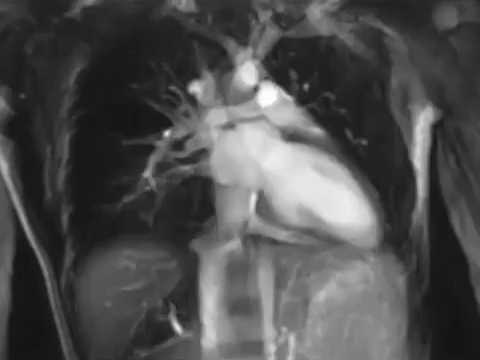

10. Серцебиття, зняте апаратом МРТ